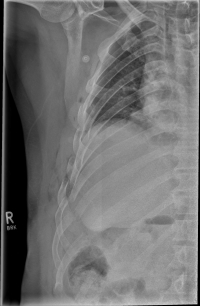

Rippenserie re                   Rippenserie re1

If three or more ribs are broken on the same side, this is called a flail chest. A rib fractured in more than one place is called a piece break.

In the case of a rib fracture, patients often experience breath-related pain, which increases especially with deep inhalation. Likewise, coughing or pressing on the affected area can be painful. Bruising on the outside (hematoma) and swelling may be visible. In rib serial fractures, there may also be the presence of an unstable thorax, which manifests itself as paradoxical breathing. That means, the opposite movement of the thorax during respiration occurs, during which the thorax contracts during inhalation and bulges outward during exhalation.

As a rule, the rib fracture is diagnosed by X-ray. In severe cases or ambiguous X-ray findings, a layer imaging, for example computer tomography (CT), can also be performed.